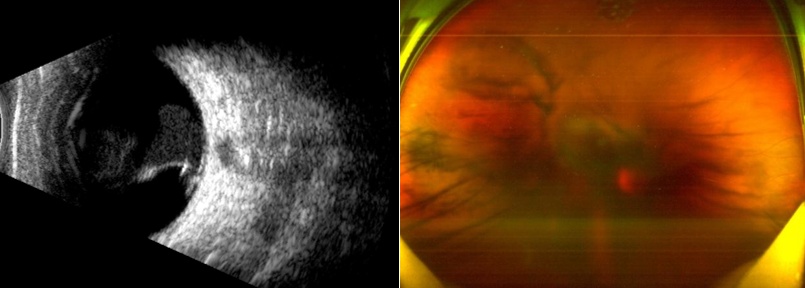

化姓张女士,34岁时在进行美容期间,由于操作存在不当之处,致其右眼受美容仪激光照射,而后出现视力急剧下降,同时还伴有眼前黑影飘动的状况,随后立刻前往哈医大二院急诊。医生快速展开检查,发现其右眼玻璃体腔内存在血性混浊的情况,并且其黄斑区出现了因外伤所导致的巨大裂孔。

SLO、B超显示右眼玻璃体积血